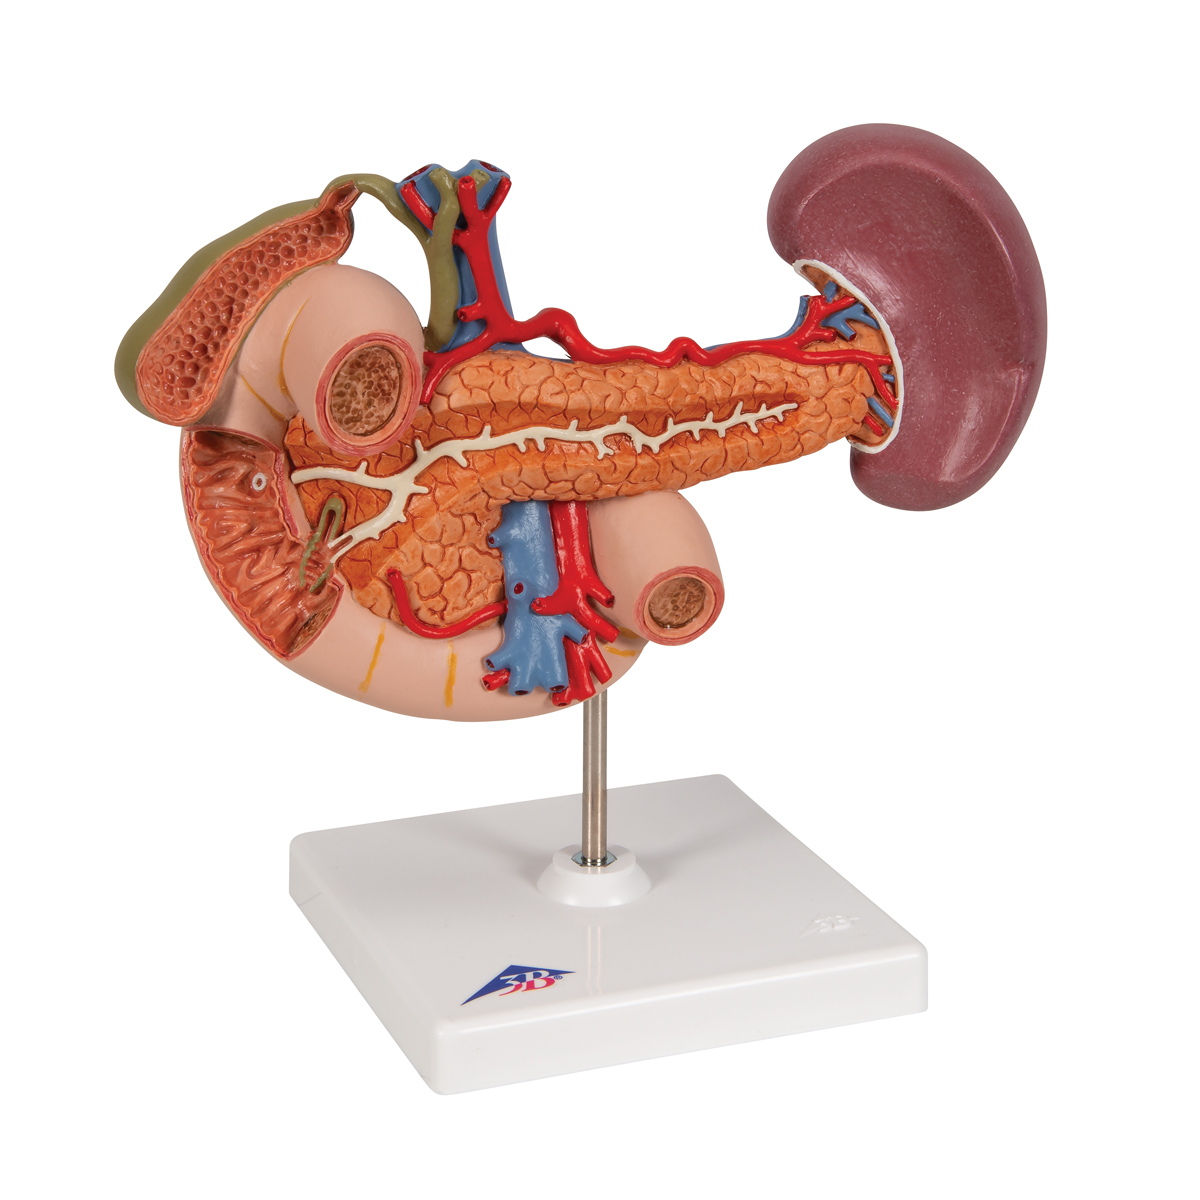

Эта модель в натуральную величину демонстрирует почки с надпочечниками, мочеточники, внутрипочечные сосуды и крупные кровеносные сосуды, расположенные в непосредственной близости от почек. Съемная передняя половина правой почки позволяет увидеть почечную лоханку, чашечки, корковый и мозговой слои почки. На подставке.